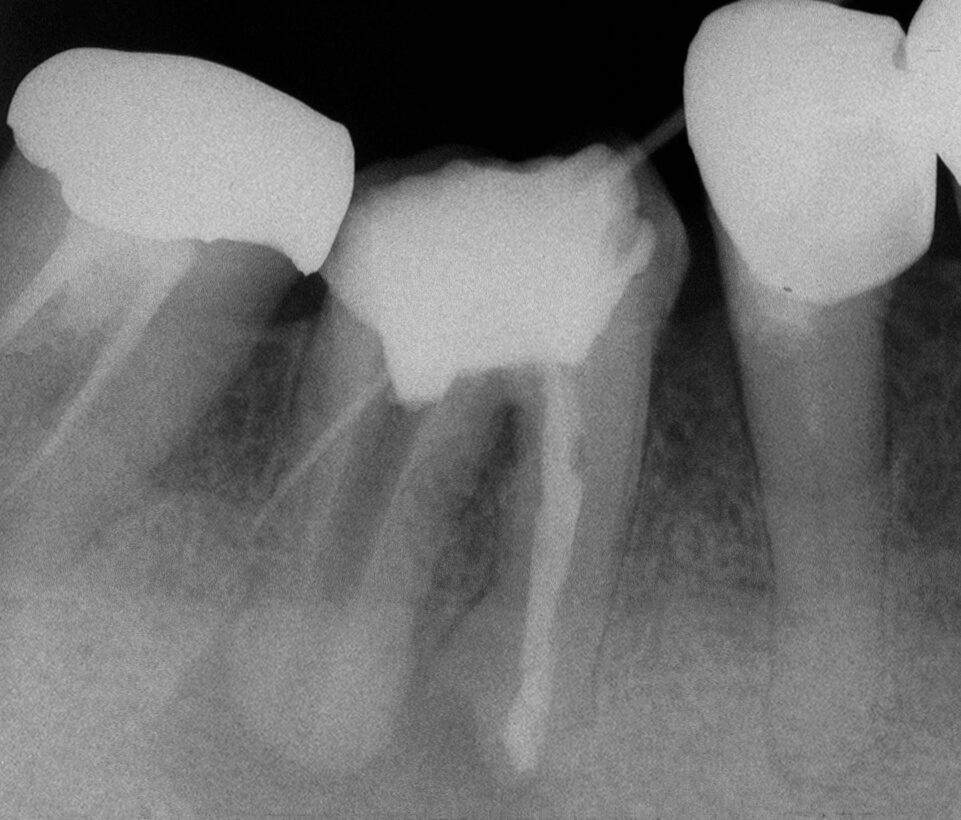

手術用顕微鏡を用いることにより、肉眼のみでは見ることのできないところを明確に観察しながら処置を行うことができます。 このことにより診断や処置の精度をより向上させることができます。歯の根の治療では通常の治療を行っても症状が改善されない場合に、 小さな根の先端部を外科的に切断除去したのち封鎖する手術(歯根端切除手術)を行うことがありますが、そのような精密な手術にも手術用顕微鏡はとても有効です。当センターでは平成19年4月より、 先進医療として、この歯根端切除手術を、診断精度の高いコーンビームCT(歯とその周囲のCT)と併用し行っていましたが、平成28年4月より保険導入されました。